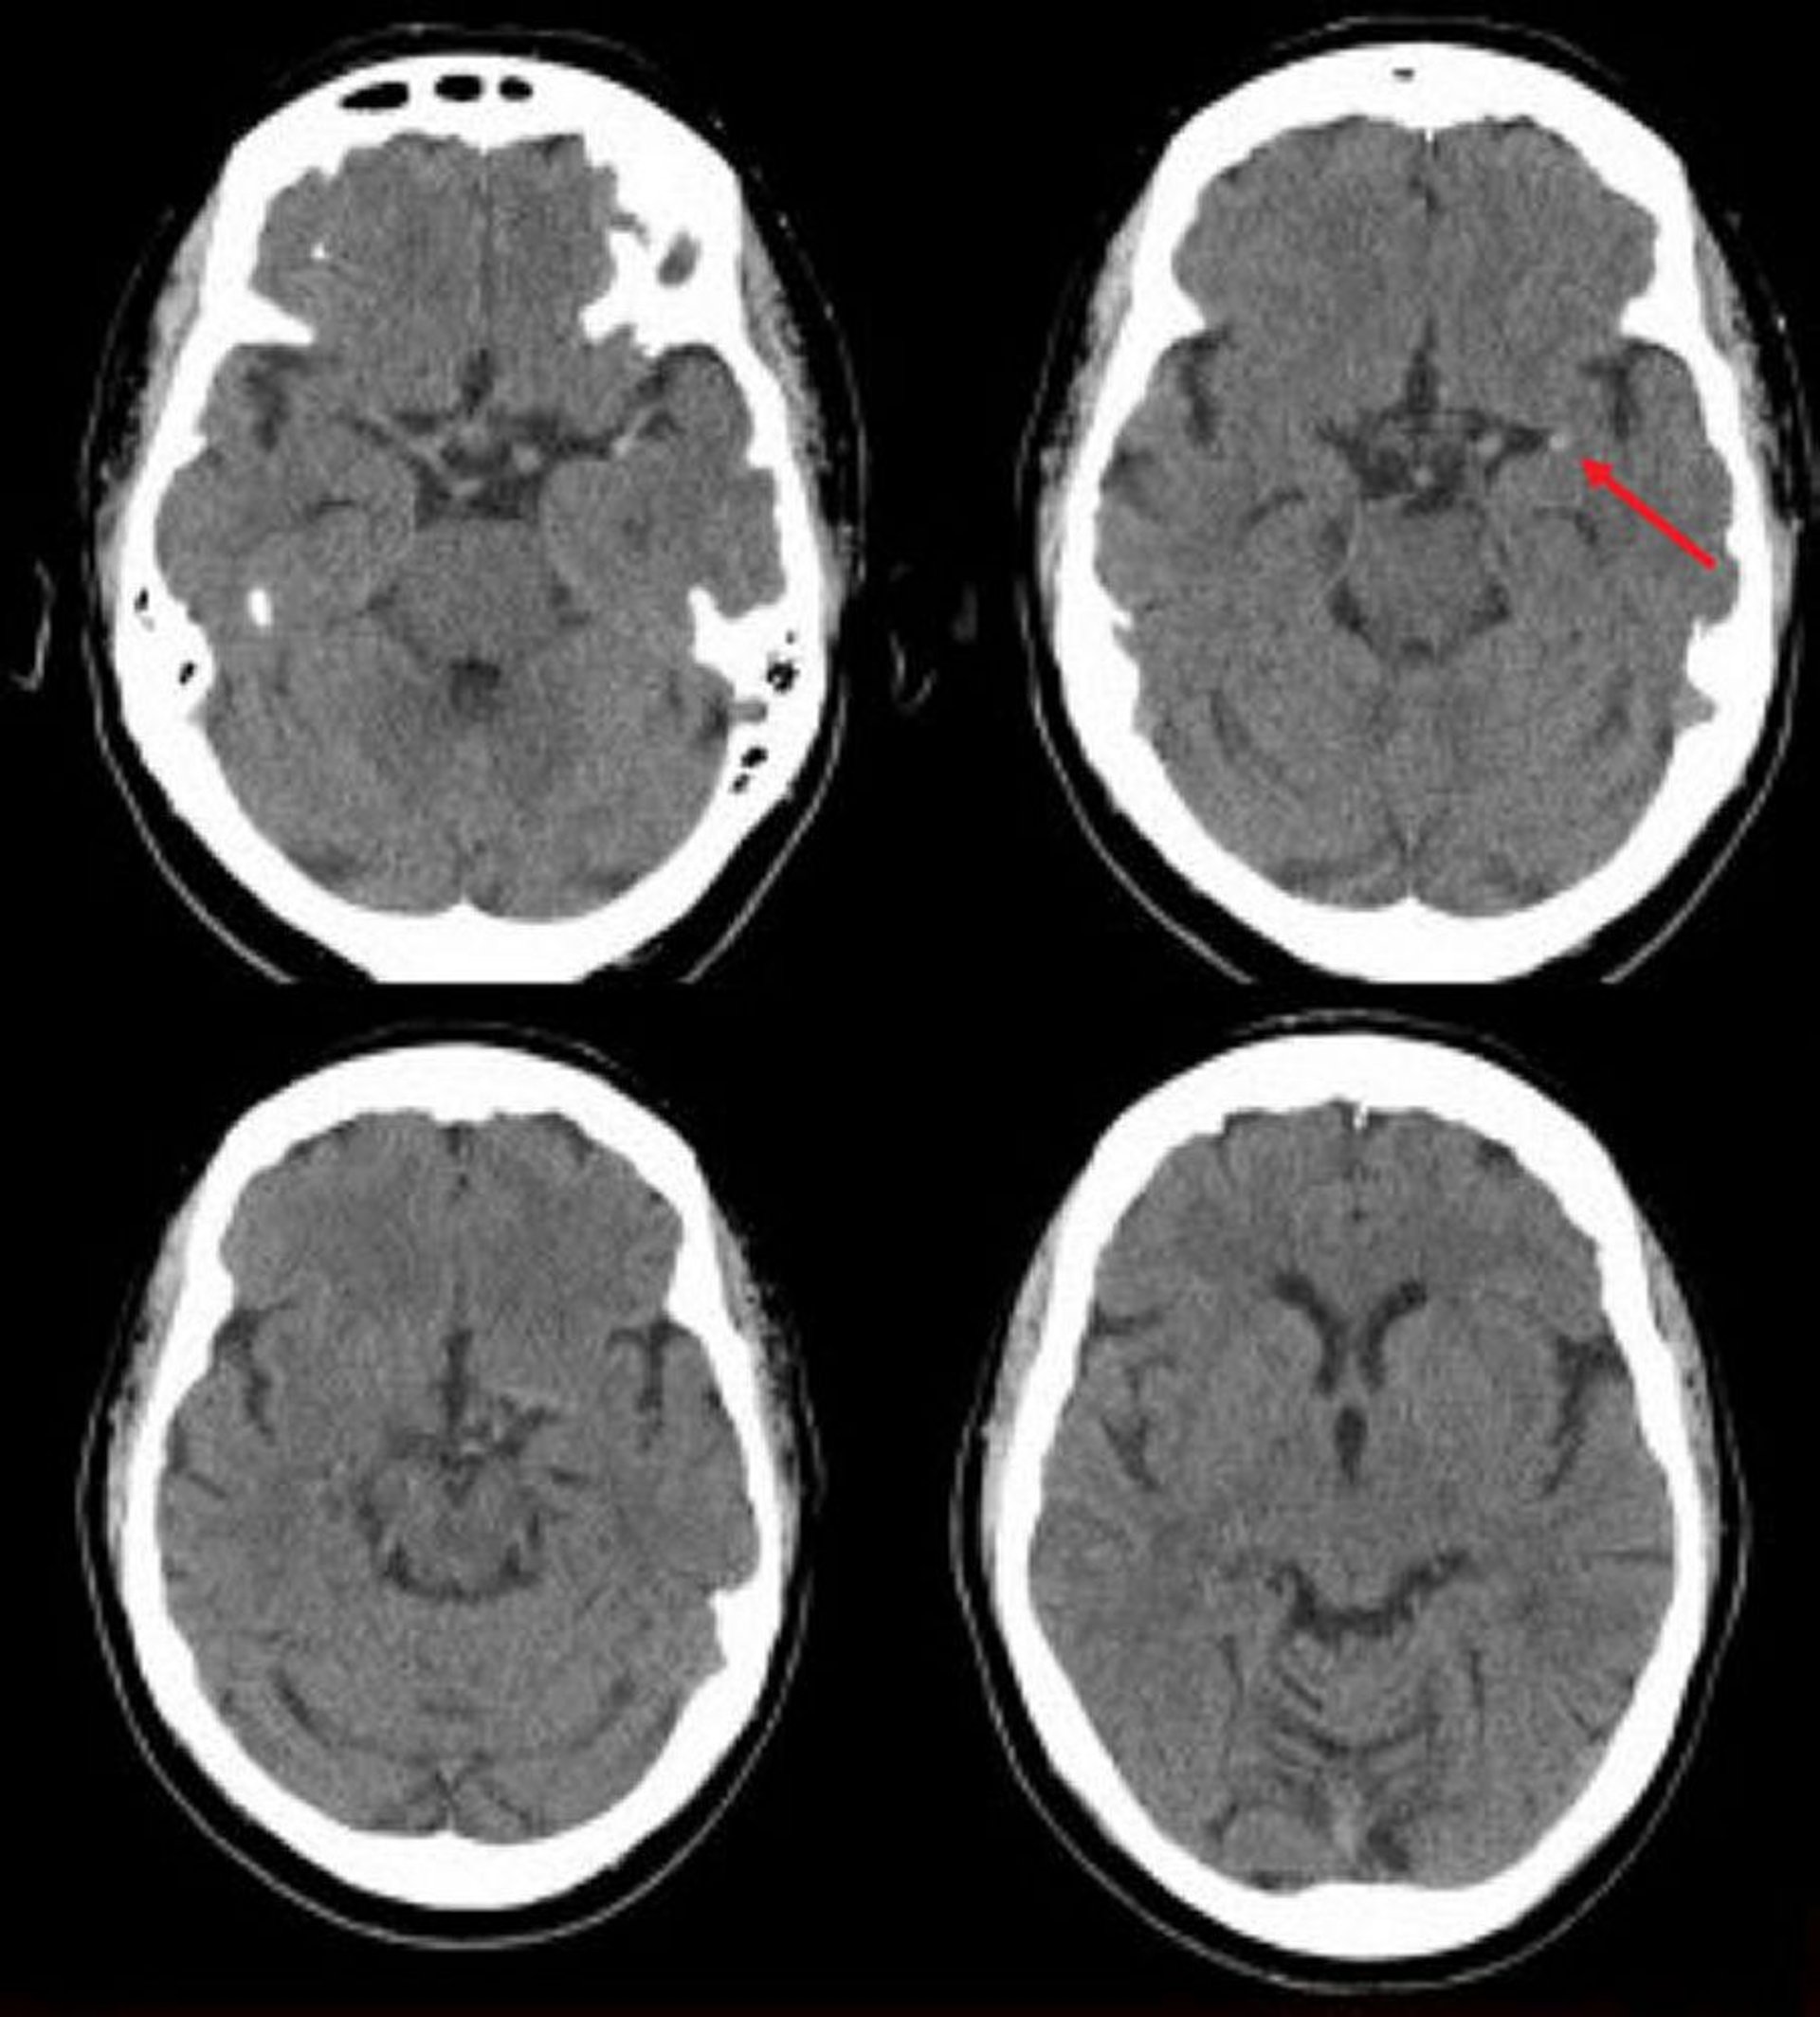

Đột quỵ do thiếu máu não cục bộ ở động mạch não giữa bên trái (CT)

Chụp CT sọ não không tiêm thuốc này cho thấy một động mạch não giữa tăng áp. Phát hiện này cho thấy một cục máu đông trong động mạch não trái (mũi tên).